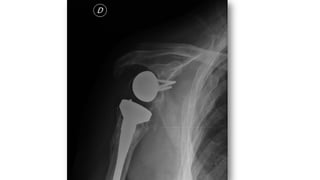

FRACTURA HUMERO

• 5% de las fracturas del adulto, 75% en 1/3 superior

• Más frecuentes en ancianos (osteoporosis)

• Tratamiento:

• Conservador: cuello quirúrgico con impactación (ancianos)

• Quirúrgico: el resto

• Complicaciones

• Seudoartrosis

• Consolidación defectuosa

• Necrosis avascular

• Lesión nerviosa ó vascular

• Rigidez-capsulitis.

• Fx diáfisis: más frecuente en jóvenes o ancianos con fx patológica

• Clasificación de Neer: relación entre troquín, troquíter,

segmento articular y diáfisis

• Divide las fracturas en función de los desplazamientos de

estos segmentos

• FX desplazada: tiene 2, 3 o 4 segmentos, fractura-luxación,

fractura articular

• Separación >1cm o ángulo >45º